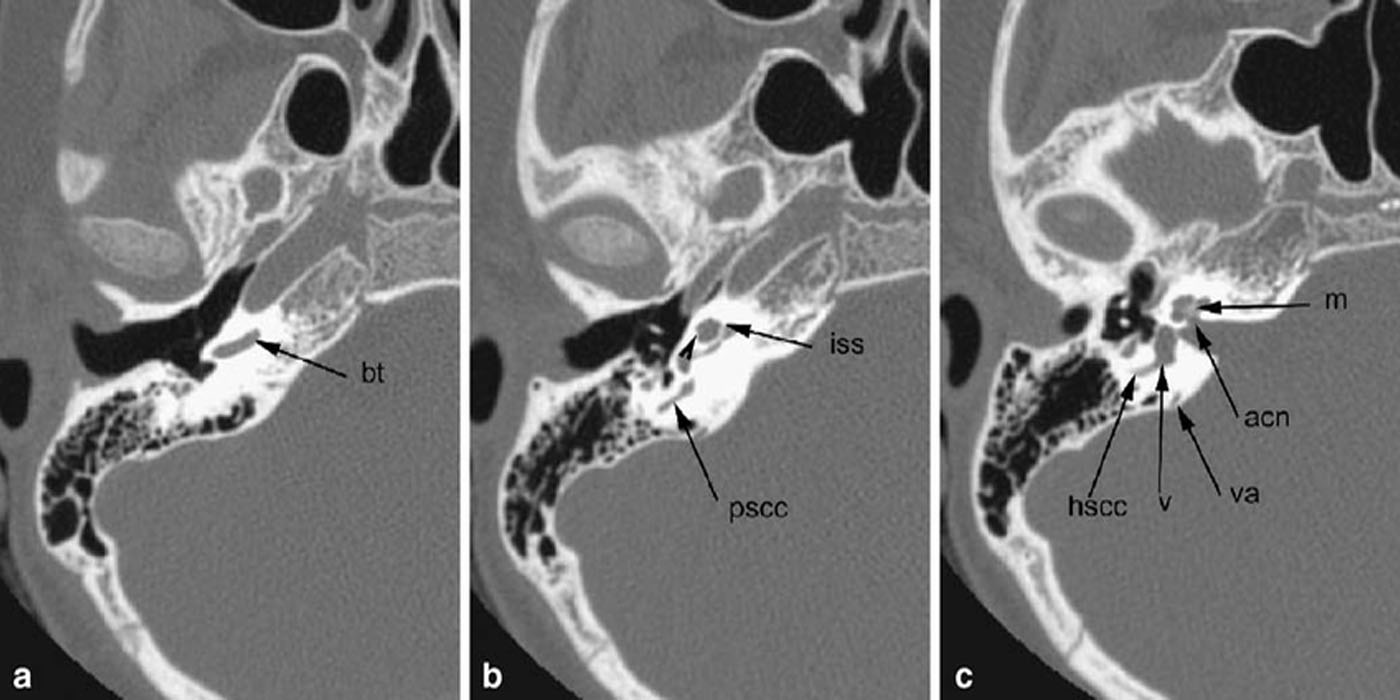

In chronic otitis with dense pars petrosa and middle ear opacity, cholesteatoma and associated complications can be diagnosed on CBCT.

Inner Ear Scan